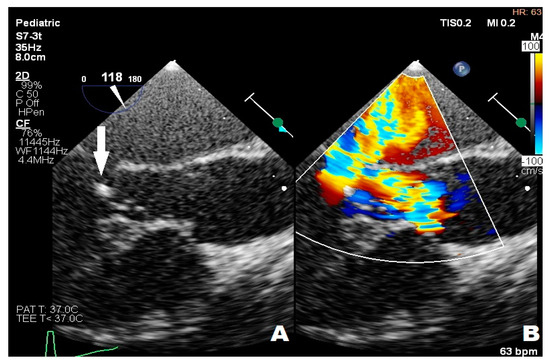

3.3. Case 3